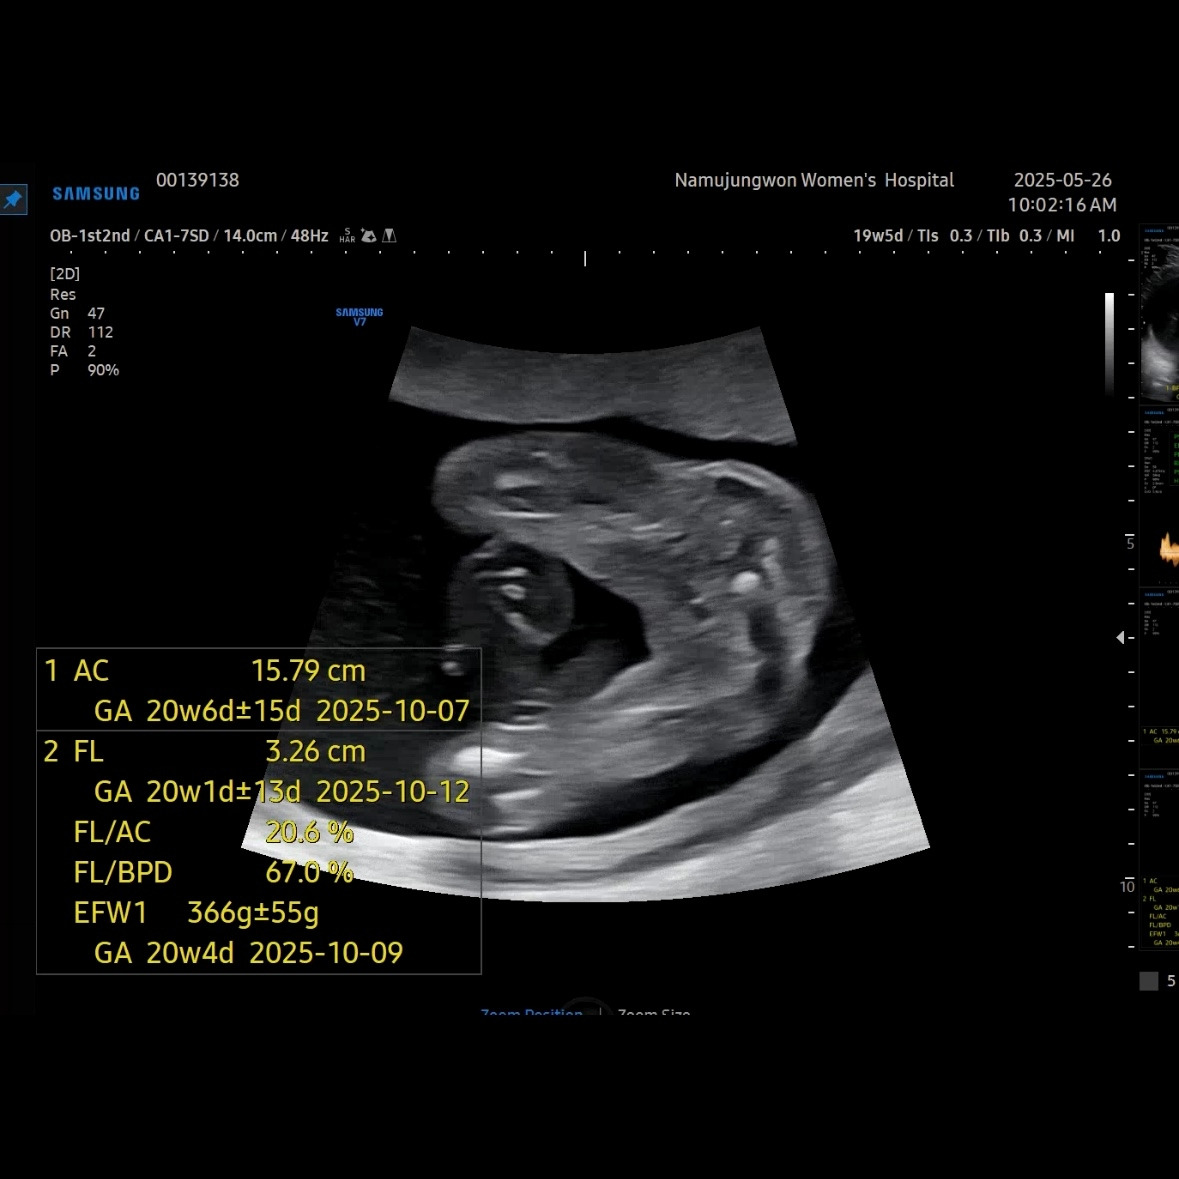

유민이 19주 5일 차에 보러 간 초음파

초음파를 보면 머리둘레, 배둘레, 허벅지 뼈길이를 꼭 재보는 데 유민이는 갈 때마다 1주 정도씩 평균보다 크게 측정된다. 1-2주 크기차이는 의미 없다고 괜찮다고 했다.

이제 얼굴이 형태가 많이 보인다. 코랑 입 위주로 보여줬다. 눈 쪽으로는 손을 올리고 있었다. 이렇게 보면 장기나 뇌나 얼굴이나 대부분 만들어져서 꽤 클 것 같이 생각되지만, 아직까지 400g이 안 되는 무게였다.

오늘로 23주 차 500g 정도로 늘었을 것이라고 한다. 다음 주에 유민이 보러 가는 날이 기다려진다. 정밀 초음파에서 얼굴도 잘 보여주기를.